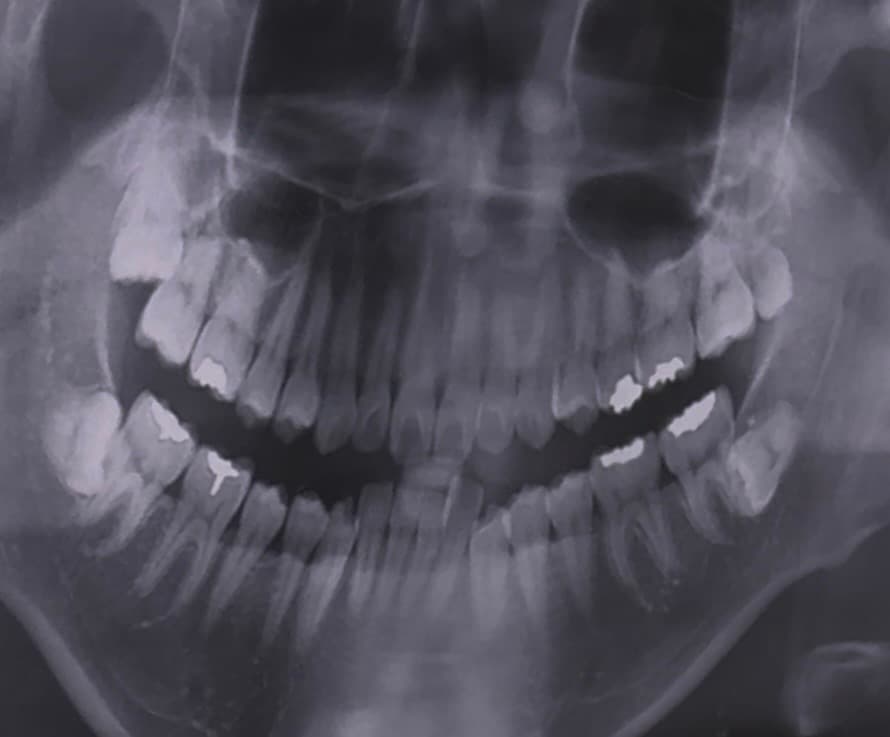

병원에서 윗쪽에 표시한 사랑니에 충치가 있다고 하는데 그냥 뽑는게 맞나요?

반듯하게 난건 나중에 스페어로 쓸수있다 그래서 고민이에요...

• 2번 째 사진